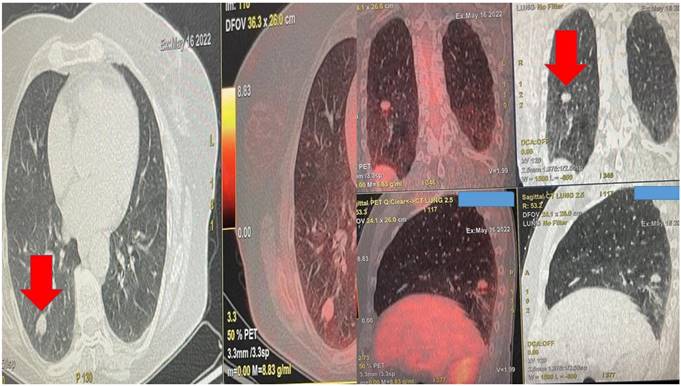

Figure 1

Demonstrates the positron emission tomography findings upon diagnosis red arrow indicates the pulmonary nodule.

Figure 2

Left upper row red arrow indicates the lesion before ablation, left lower row demonstrates the lesion sign with radial ebus, right upper row red arrow indicates the area after 2 sessions of thermal effect with radiofrequency ablation, right lower row demonstrates the lesion sign after the ablation.